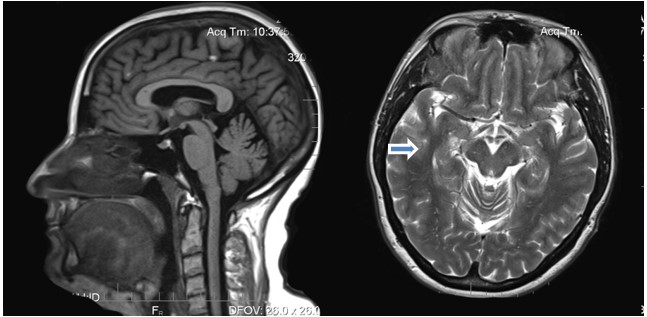

Жалобы появились в 2023 году, когда впервые пациентка стала замечать несистемное головокружение и, как следствие, неустойчивость при ходьбе. Коллеги по работе отметили появление шепелявости, однако сама пациентка не замечала за собой нарушений речи. По ночам появился храп. Пациентка лечилась по месту жительства в терапевтическом стационаре, где проходила лечение следующими препаратами: р-р цитиколина внутривенно капельно, р-р этилметилгидроксипиридина сукцинат внутривенно, таб. глицин и таб. бетагистин. Пациентка не отметила какого-либо эффекта. В апреле 2024 года появилось резкое ухудшение речи с невозможностью выговаривать слова в течение суток, за экстренной медицинской помощью не обратилась, после спонтанного улучшения самостоятельно выполнила МРТ-исследование головного мозга, где выявлены монофокальные глиозные изменения белого вещества головного мозга, неспецифического (дисциркуляторного?) генеза. После консультации невролога по месту жительства выставлен диагноз: «Вестибуло-атакический синдром, дифференциальная диагностика с дисциркуляторной энцефалопатией цервикогенного генеза, демиелинизирующим заболеванием, соматоформной дисфункцией на фоне тревожно-депрессивного расстройства». Назначено лечение: р-р депротеинизированный гемодериват крови крупного рогатого скота (актовегин) внутривенно, таб. экстракт Гинкго билоба (танакан) 40 мг, таб. буспирон (веспирейт) 15 мг и таб. пароксетин 20 мг в течение месяца, однако без эффекта. В августе 2024 г. снова проведен курс лечения - р-р инозин+никотинамид+рибофлавин+янтарная кислота (цитофлавин) в/в, р-р этилметилгидроксипиридина сукцинат (мексидол) в/в, таб. бетагистин и вновь без эффекта. Консультирована неврологом консультативно-диагностической поликлиники Иркутской областной клинической больницы от 04.09.2024 г., Заключение: «Вегетативно-сосудистая дистония, тревожно-депрессивный синдром с диссомнией». На момент осмотра вестибуло-координаторных и атактический нарушений не выявлено». Психолог от 04.09.2024 г.: «Снижение эмоционально-волевой сферы (тревожно-депрессивный фон)». В течение последующего года самочувствие ухудшилось, симптомы постепенно усиливались. Тест МОСА (амбулаторно): 19 баллов из 30. При УЗИ щитовидной железы от 08.04.24 г.: «Узел правой доли - TRADS 2». Гормоны щитовидной железы в пределах нормы. УЗИ БЦА от 22.04.24 г.: «Атеросклероз сонных артерий с локальным стенозом в бифуркации справа 25 %, слева 20 %». Консультация офтальмолога 13.09.24 г.: «Гиперметропия слабой степени тяжести, пресбиопия обоих глаз». МРТ головного мозга по протоколу диагностики нейродегенеративных заболеваний от 16.12.2024 г. (Рисунок 2): «Структурных изменений головного мозга, избирательной гиппокампальной атрофии, данных за болезни Паркинсона и Альцгеймера не выявлено». Для уточнения диагноза направлена в неврологический стационар Иркутского государственного медицинского университета с 17.01.25 по 27.01.25 г. Выписана с диагнозом: «Нейродегенеративное заболевание с преимущественным вовлечением мозжечковых структур, зоны гиппокампа, надъядерных структур, мозжечковый синдром (атаксия, дисметрия, нистагм, дизартрия), элементы псевдобульбарного синдрома (положительные рефлексы орального автоматизма), умеренные когнитивные нарушения (шкала МОСА 18 баллов), элементы акинетико-ригидного синдрома (ахейрокинез, гипомимия, шаркающая походка), диссомнический синдром».

Рис 2. МРТ головного мозга пациентки М., 52 года. Возможный симптом «Мики-Мауса» (указано стрелкой авторами статьи).

Fig. 2. MRI of а 52- year-old female patient M. Possible "Mickey Mouse" symptom (indicated by arrow by the authors of the article).

Наиболее ярким и существенным феноменом является диссоциация клинических проявлений с данными нейровизуализации. Две пациентки, примерно одного возраста, с приблизительно одной длительностью заболевания и степенью выраженности клинической картины демонстрируют разную степень поражения и вовлеченности структур головного мозга по данным МРТ диагностики: если в первом случае у пациентки с классической картиной ПНП обнаружены симптомы «Микки-Мауса» и «колибри», то во втором случае на фоне выраженной картины поражения головного мозга, МРТ изображения не демонстрируют характерных признаков.

Представленная клиническая картина надъядерного пареза вертикального взора (особенно, при взгляде вниз), ранних постуральных нарушений с падениями назад, псевдобульбарного синдрома, аксиальной ригидности в сочетании с характерными изменениями на МРТ (симптом "колибри", "Мики-Мауса") с высокой долей вероятности указывает на прогрессирующий надъядерный паралич (синдром Ричардсона) по критериям шкалы MDS (2017) для пациентки Ж.: О1+Р1, дополнительные критерии - А2, С2, СС2, IF1, для пациентки М.: О1+Р2, дополнительные критерии А2, С1-2, СС2. Недостаточная или отсутствующая эффективность ответа на терапию леводопой и неуклонное прогрессирование симптоматики подтверждает нейродегенеративную природу заболевания. Дальнейшая тактика должна быть направлена на симптоматическое лечение, реабилитацию и поддержку пациента и его семьи.